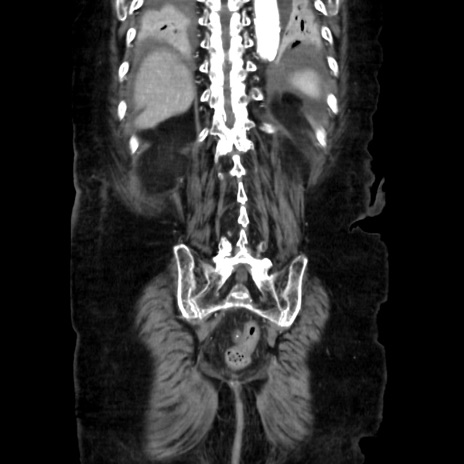

症例40(冠状断像)

【症例】90歳代女性

【主訴】腹痛・嘔吐

【現病歴】 食欲低下、嘔吐があり昨日他院受診。肺炎と診断され入院となる。入院後より腹部全体に圧痛あり。胃管留置され経過みていたが、症状持続するため、

当院転院となる。

【既往歴】胸椎圧迫骨折、胆石症

【身体所見】腹部:中央に激痛あり、圧痛あり、反跳痛不明

【データ】WBC 17100、CRP 18.82

冠状断像